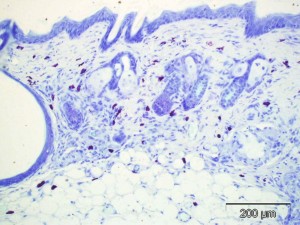

CBI offers a robust validated murine model of atopic dermatitis characterized by edema, perivascular eosinophil and monocyte inflammation, and increased epidermal thickness in taped stripped skin that has been repeatedly sensitized with albumin. The skin is sensitized and challenged by ovalbumin to induced a chronic sensitization that recapitulates the human and veterinary condition. The photomicrographs present the typical histopathology of this model in mice. The toluidine blue stain shows the increases in mast cells in the affected areas. The HE stain demonstrates the typical dermal fibrosis, multifocal inflammation and epidermal hyperplasia found in this model.